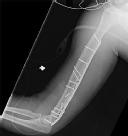

Question 7:

A 25-year-old manual laborer presents with 6 months of radial-sided wrist pain. He recalls a fall on an outstretched hand approximately one year ago but did not seek medical attention at the time. Radiographs demonstrate a scaphoid waist nonunion with sclerosis and cystic changes, but there is no evidence of radioscaphoid or midcarpal arthritis. What is the most appropriate surgical treatment?

Correct Answer: Open reduction internal fixation with bone grafting

Explanation:

The patient has a scaphoid nonunion but lacks degenerative arthritic changes (this is pre-SNAC or SNAC stage 0). In the absence of arthritis, the goal is to obtain union of the scaphoid to prevent the progression of carpal collapse and arthritis. This is best achieved via ORIF with bone grafting (non-vascularized or vascularized, depending on proximal pole viability). Salvage procedures like four-corner fusion or PRC are reserved for established SNAC arthritis.